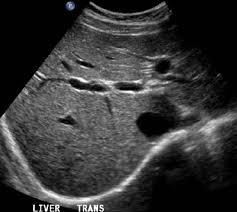

Η διάγνωση της αλκοολικής νόσου του ήπατος πολλές φορές δεν είναι εύκολη, κυρίως επειδή οι ασθενείς υποτιμούν την ποσότητα αλκοόλ που πίνουν και πολλές φορές κρύβουν την αλήθεια. Επίσης οι εργαστηριακές εξετάσεις και η κλινική εικόνα δεν δείχνει πάντα ξεκάθαρα ευρήματα γιατί τα ίδια μπορεί να φανούν και σε άλλες παθήσεις. Σε γενικές γραμμές οι τρανσαμινάσες (ιδίως η AST) καθώς και η ggt είναι αυξημένες και στον υπέρηχο μπορεί να φανεί πως το ήπαρ είναι διογκωμένο, ότι έχει λίπος, ή στα πολύ προχωρημένα πως έχει κίρρωση ή καρκίνο.